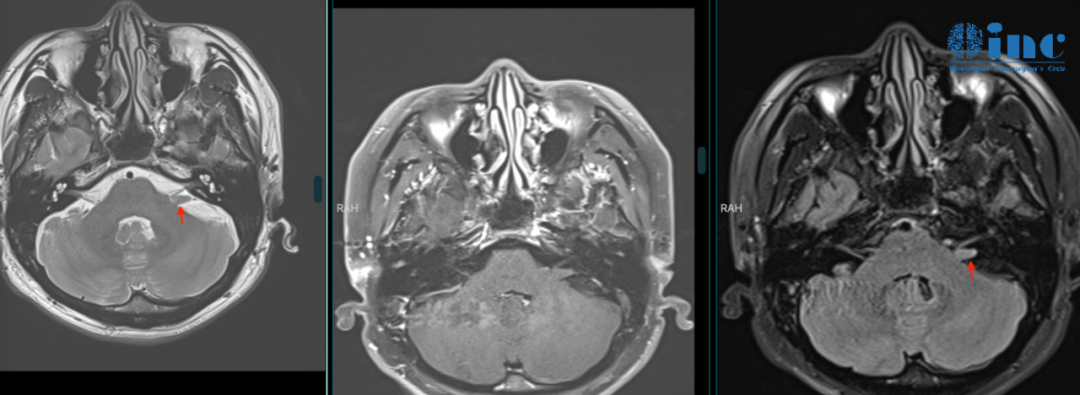

橙子先生2023年1月脑MR检查

影像学检查

MRI表现:MRI增强扫描是诊断听神经瘤的首选方法,可显示内听道内的微小听神经瘤,在Tl加权像呈低信号或等信号,T2WI呈不均匀高信号,增强后呈不均匀强化,囊变坏死常见。